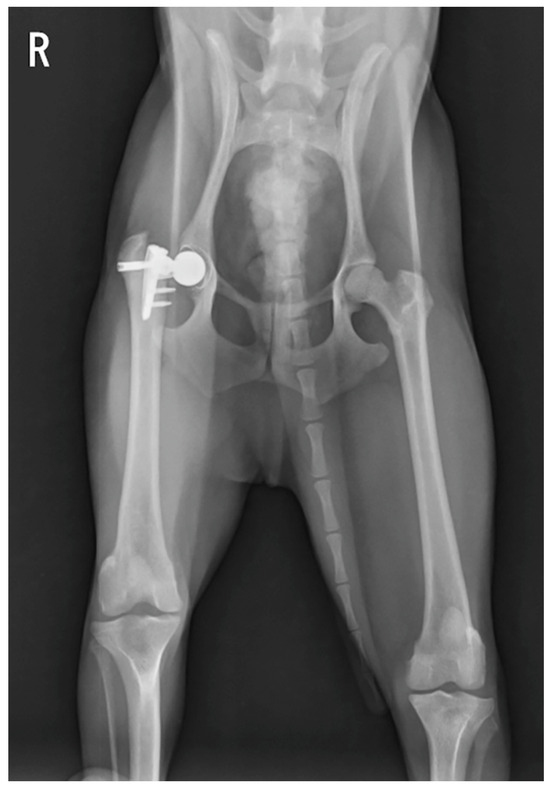

Figure 4.

Postoperative radiographs 2 months after reimplantation: (a) ventrodorsal view; (b) yoga view (Cr-Cd view tangent to the stem).